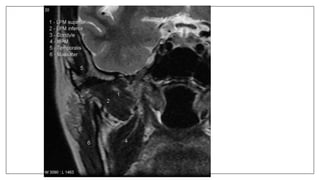

Pathologies